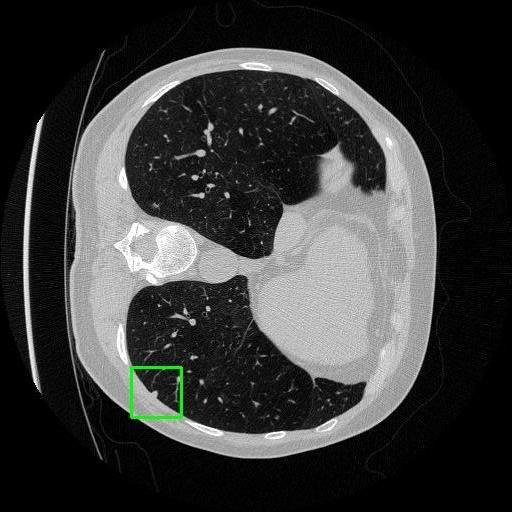

We developed an AI-based system using deep learning models for analyzing lung CT scans to detect and classify pulmonary nodules. We chose the YOLOv11 architecture for its enhanced object detection capability and adapted it specifically for medical imaging, incorporating pixel-level precision and severity classification.

Classification into three severity levels with colored bounding boxes.

Maintaining performance on small, complex features like micro-nodules tested the limits of traditional object detectors.

Successfully built and deployed an AI model (YOLOv11) capable of detecting lung nodules in CT scans with high accuracy and real-time performance.

Designed a severity classification system that categorizes nodules into null, moderate, and severe using colored bounding boxes, assisting in rapid clinical decision-making.